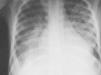

Se trata de un varón de 10 años que se remite a urgencias por dificultad respiratoria. Presenta dificultad respiratoria y astenia progresiva de 2 semanas de evolución con empeoramiento en los últimos 2 días, sin clínica catarral ni fiebre. Niega haber estado en contacto con tóxicos, plantas o animales, así como haber realizado viajes recientes. Durante el traslado al hospital se le administra salbutamol inhalado y adrenalina nebulizada y subcutánea, sin apreciarse respuesta favorable. De sus antecedentes destaca una distocia social importante, prematuridad con bajo peso, falta de seguimiento del calendario vacunal, un ingreso por bronquiolitis y una faringoamigdalitis (tratada con amo-xicilina durante 2 semanas) 2 meses antes del proceso actual. En la exploración realizada al ingreso se observa peso de 28kg, talla de 133cm, frecuencia respiratoria de 60rpm, frecuencia cardíaca de 84lpm, presión arterial de 167/105mmHg, saturación de oxígeno del 86% (fracción inspiratoria de oxígeno [FiO2] del 21%), mal estado general, distrés respiratorio intenso, leve edema en tobillos y pies, e hipoventilación en ambas bases pulmonares. De los exámenes complementarios, destaca: analítica de sangre con leucocitos de 13,9×109/l (neutrófilos 75,9%), urea 37mg/dl, creatinina 0,64mg/dl (filtrado glomerular estimado por talla 114,3ml/min/1,73m2), colesterol y triglicéridos normales, proteínas totales y albúmina en plasma de 68,2/34gr/l, iones y proteína C reactiva normales; la microhematuria y la proteinuria en orina de micción son de 4,4mg/mg (rango nefrótico). En la radiografía de tórax se observa condensación hiliofugal algodonosa bilateral y derrame pleural bilateral (fig. 1); la ecocardiografía muestra dilatación de ventrículo izquierdo pero función conservada. El paciente ingresa con el diagnóstico de infección respiratoria, edema pulmonar y síndrome nefrítico. Se inicia tratamiento con oxigenoterapia (FiO2 50%), macrólido, nifedipino y furosemida, y el paciente presenta mejoría clínica sobre todo con el tratamiento deplector. En estudios posteriores, destaca: analítica sanguínea completa inespecífica con creatinina de 0,82mg/dl (control a las 24h), orina con extracción fraccionada de sodio (EFNa) del 0,9%, superior a 100 hematíes con el 35% de dismórficos; proteínas y creatinina de 0,9 en la orina de la micción a las 24h y proteinuria de 7,6mgs/m2/h con aclaramiento de creatinina de 125ml/min/1,73m2 en la orina minutada a las 48h; líquido pleural compatible con trasudado, pruebas funcionales respiratorias de características restrictivas, tóxicos en orina, prueba de Mantoux, cultivos y serologías negativos; inmunología con anticuerpos antinucleares positivos de valor moderado, disminución global del complemento y anticuerpos antiestreptolisina O (ASLO) de 1.400U/ml. Ante los antecedentes de faringoamigdalitis, elevación de ASLO, complemento disminuido, EFNa inferior al 1% y síndrome nefrítico sugerido por la hematuria, edemas e hipertensión arterial, el diagnóstico se orienta como glomerulonefritis aguda postestreptocócica (GNAPS) de presentación atípica con edema agudo de pulmón (EAP). La evolución posterior del paciente es favorable, siendo dado de alta a los 8 días; presenta normalización del complemento a las 3 semanas que confirma el diagnóstico.

Es común orientar inicialmente como neumonía el cuadro de distrés respiratorio e infiltrados alveolares con derrame pleural en la radiología6. El diagnóstico diferencial engloba etiologías infecciosas, cardíacas, tóxicos, causas tumorales y otras etiologías de síndrome pulmonar y renal, como procesos autoinmunitarios del tipo de la vasculitis o del lupus. El diagnóstico de GNAPS y el tratamiento precoz del EAP, consistente principalmente en conseguir una adecuada diuresis, puede disminuir el número de tratamientos y procedimientos intervencionistas6–8. El pronóstico de la GNAPS en niños es excelente si ésta es adecuadamente diagnosticada y tratada; no obstante, la mortalidad precoz puede llegar hasta el 25% en pacientes que presentan EAP como complicación7,9.